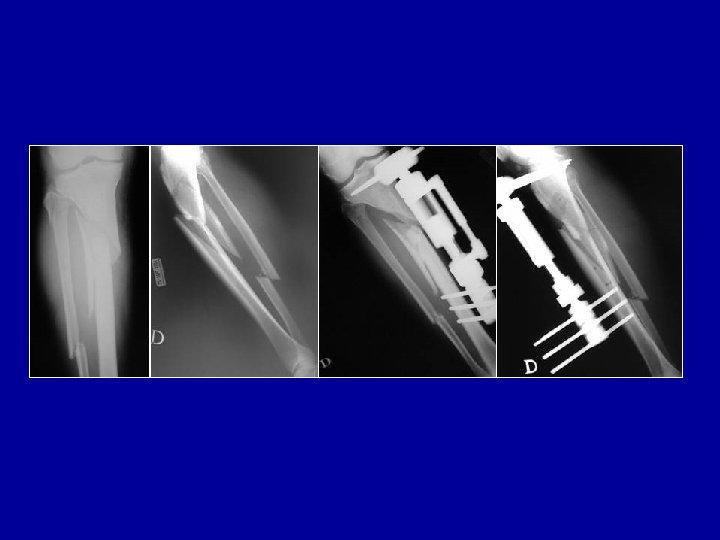

Traitement chirurgical des inégalités des membres: Allongement du tibia Allongement progressif par fixateur externe en cadre Allongement par fixateur de Wagner puis greffe et remplacement du fixateur par une plaque

Traitement chirurgical des inégalités des membres Allongement du fémur Allongement par fixateur de Wagner puis greffe et remplacement du fixateur par une plaque